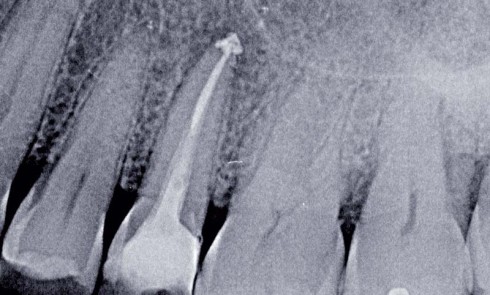

Article réservé à nos abonnés Les fractures radiculaires des dents permanentes

Les fractures radiculaires représentent 0,5 à 7 % des traumatismes en denture permanente. On les observe surtout chez les sujets...